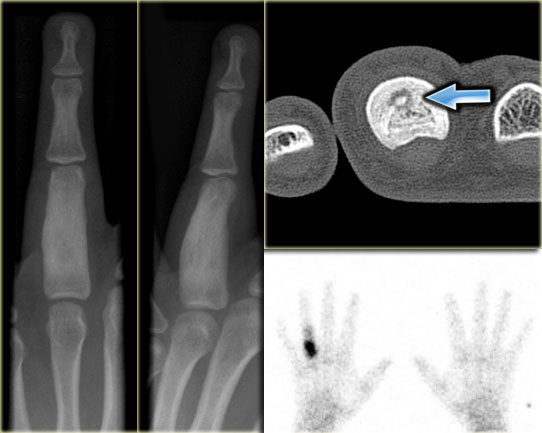

Here images of a male patient, 18 years of age, with complaints of pain, particularly at night in the fourth digit.

Plain radiograph shows extensive sclerosis and broadening of the proximal phalanx.

CT shows a small lucency with central calcification and extensive sclerosis of the bone marrow.

Scintigraphy reveals intense focal activity.

The CT findings are pathognomonic for an osteoid osteoma.